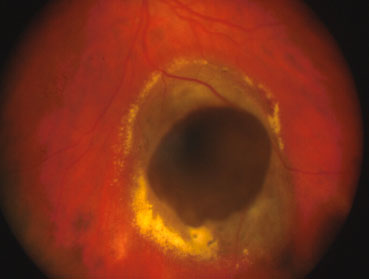

La diagnosi di melanoma coroideale è essenzialmente clinica. La diagnosi differenziale con le altre lesioni pigmentate uveali (nevo, melanocitoma, ipertrofia dell'epitelio pigmentato retinico, emorragia coroideale, neovascolarizzazione, eccetera) si basa sulla valutazione oftalmoscopica da parte di un oftalmologo esperto.

Gli esami strumentali accessori utilizzati sono l'angiografia a fluorescenza e/o con verde indocianina e l'ecografia oculare A/B scan.

Le diagnosi differenziali più impegnative riguardano i tumori amelanotici (nevi, emangiomi, metastasi, osteomi) e quei casi in cui non è possibile visualizzare la lesione a causa dei mezzi diottrici non trasparenti (leucomi corneali, cataratta, emovitreo, distacco di retina).